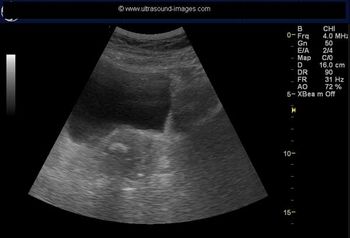

New research shows that symptoms exist in even early-stage ovarian cancer, disproving the myth that it's a "silent killer." Barbara Goff, MD, presents the latest in symptom research, tips on what physicians should be looking for, and what's on the horizon for ovarian cancer screening.